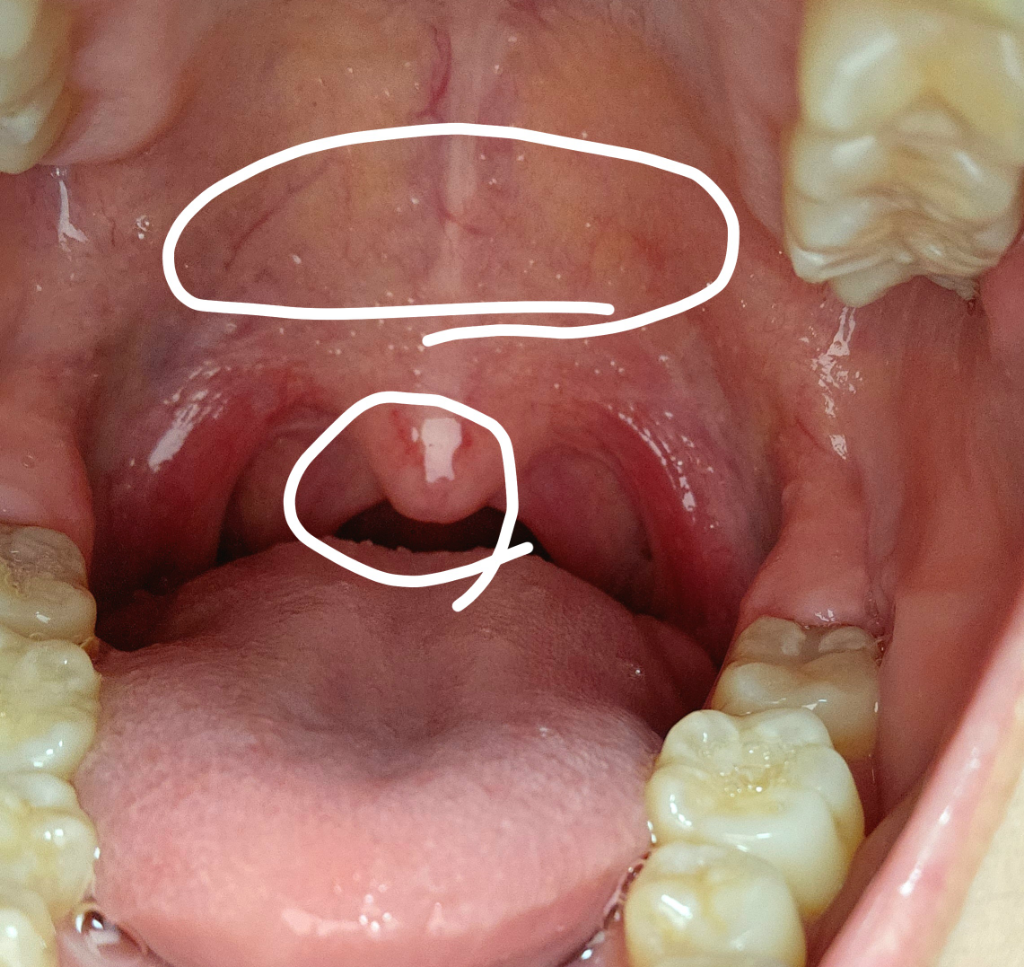

구강건조증 등으로 인한 증상의 가능성 및 역류성 식도염 등으로 인한 인후불편감의 가능성도 있겠습니다.

우선 증상발생시 이비인후과에 내원하시어 정확한 진단 및 약물처방을 받으시는 것을 추천드립니다.